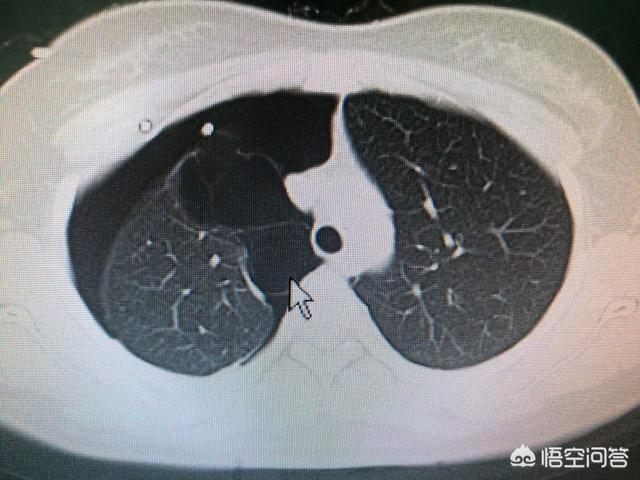

2. examen tomodensitométrique des poumons.L'examen tomodensitométrique des poumons permet d'observer la gravité de la bronchite chronique ainsi que l'emphysème dans les poumons, ce qui permet de déterminer indirectement la gravité de l'état du patient.

Pour le diagnostic du cancer du poumon, la méthode de diagnostic la plus importante est l'imagerie. La radiographie du thorax permet de détecter le cancer du poumon avec des lésions plus importantes, mais pour les cancers du poumon plus petits, il est toujours nécessaire de passer l'examen médical.Tomodensitométrie du thoraxpour poser un diagnostic. Un scanner du thorax est également le meilleur moyen de dépister et de diagnostiquer le cancer du poumon. En outre, il est souvent possible deBronchoscopie à fibres optiques ou ponction guidée par CTDes examens tels que le prélèvement de tissu de la lésion et la réalisation d'une biopsie pathologique permettent d'établir le diagnostic de référence.

En cas de suspicion de pneumothorax, le premier examen est l'imagerie, principalementRadiographie thoracique et tomodensitométrie thoracique. Une radiographie du thorax suffit généralement à confirmer la présence d'un pneumothorax et, pour certains patients, un scanner du thorax peut être réalisé.